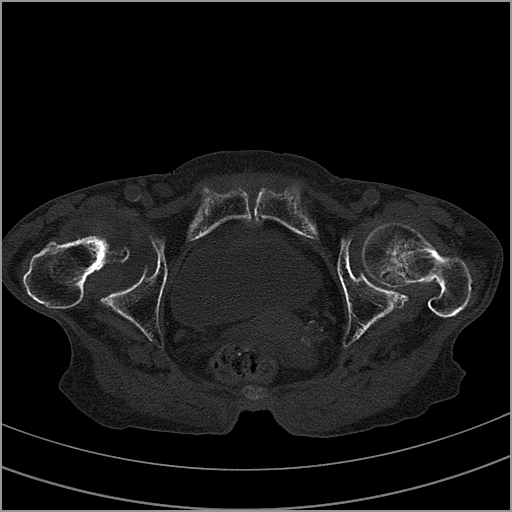

以下是引用老爱克斯新网客在2009-2-3 19:42:00的发言:[br]右侧髋臼及右侧股骨头可见明显骨质破坏,以溶骨性破坏为主,无明显硬化,髋关节间隙变窄,周围软组织明显肿胀,密度不均,脂肪间隙消失。[br] 诊断:右侧髋关节感染性病变,右侧髋关节结核的可能大。[br] 鉴别诊断:1.股骨头缺血坏死,单纯股骨头缺血坏死病例不会累积髋臼骨破坏。2。退行性关节炎,以骨质增生为主,伴有关节面硬化,骨质破坏呈多发小囊状破坏为主,其周围可见硬化环。3.股骨头缺血坏死晚期(第四期)骨质破坏可伴髋关节退行性变,可有骨质增生,但此时骨破坏以股骨头破坏为主,不应该伴有髋臼骨质破坏,因为股骨头的骨破坏是因血运中断,而没有髋臼的血运中断,又没有细菌的感染,怎么能造成髋臼的骨破坏呢。